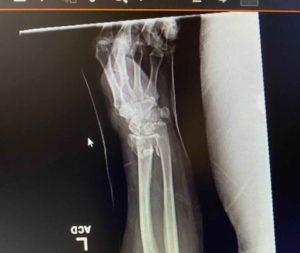

When she called me, of all her injuries, it was the broken left arm that was the most painful. Fracturing the wrist and elbow, she explained that she had Complex Regional Pain Syndrome, and described it like a sunburn, with acid being put on it. Fortunately, she had already recovered from 13 years of chronic pain with Block Therapy and knew how to breathe. She shared that this was her saving grace during the month in the hospital.

The prognosis wasn’t good. They suspected she wouldn’t walk again and never be able to have normal function with her left hand. Here are some photos showing the extent of her fractures at the time of injury.